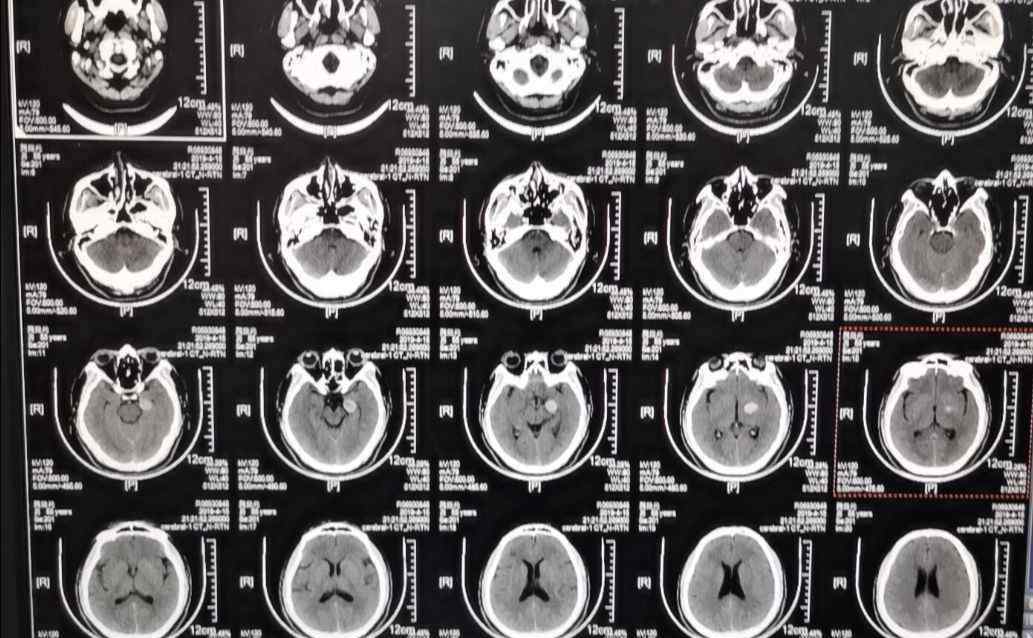

患者魏继光,突发一过性头晕起病。于208医院行头部CT

入我院后复查CT

可见局部高密度影像学表现,考虑颅内动脉瘤可能性大